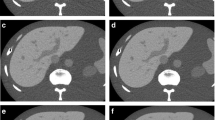

Three independent board-certified radiologists (two thoracic radiologists [J.H.H. and D.S.K.] and one general radiologist [J.S.O.], with 5–7 years of experience in the interpretation of chest CT imaging) evaluated the image quality of each reconstructed image. For each case, two reconstructed image sets were anonymized and distributed in random order for thoracic evaluation, and three image sets were provided for the evaluation of the upper abdomen. Only overlapping parts (from the basal lung level to the kidney level) were selected and provided for the evaluation of the upper abdomen. The readers were blinded to information on the reconstruction technique and the clinical indication. For each image set, subjective image noise, spatial resolution, presence of artifacts, and overall image quality were evaluated for both the thoracic and upper abdominal images, following previous studies [13, 14]. An example of a distortion artifact observed in DLIR-reconstructed images is provided in Fig. 2. The readers then selected the most preferred algorithm for image interpretation. Detailed information on the scale used for image evaluation is provided in Table 2.

An example of a distortion artifact observed on a deep learning–based image reconstruction (DLIR-CHT) scan. A 71-year-old male patient receiving postoperative surveillance for advanced gastric cancer underwent contrast-enhanced chest and abdominal CT scans. DLIR-reconstructed chest CT images (a, b) showed diffuse checkered line-like artifacts. One out of three readers assessed that these artifacts diminished the diagnostic performance of the image (score 1). Those artifacts were not visualized on adaptive statistical iterative reconstruction (ASiR)-reconstructed abdominal CT images (c, d)